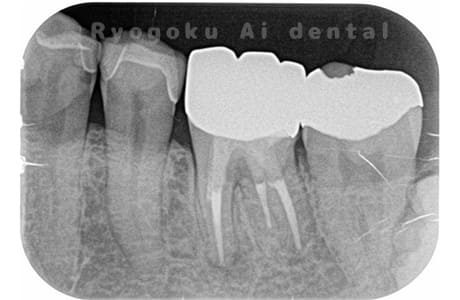

Case02

- 原因

- 慢性根尖性歯周炎

- 治療期間

- 3ヶ月

- 治療内容

- マイクロエンド

- 治療費用

- 121,000円

噛むと痛みが出る、とのことで来院した患者様です。他院での根管治療を終えてましたが、根尖病変を認めるため、マイクロエンドを行いました。

<リスク・副作用>

術後は痛み、腫れ、痺れなどの副作用が生じる場合があります。症状が再発する可能性があります。